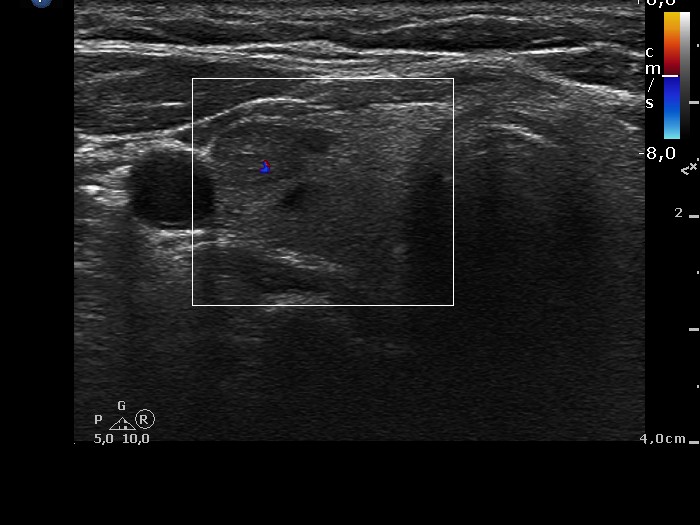

Ultrasonography: The thyroid was minimally hypoechogenic. There were several small cystic areas in both lobes and a moderately hypoechogenic, inhomogeneous lesion in the right lobe. The latter displayed no vascularity and was aspirated previously.